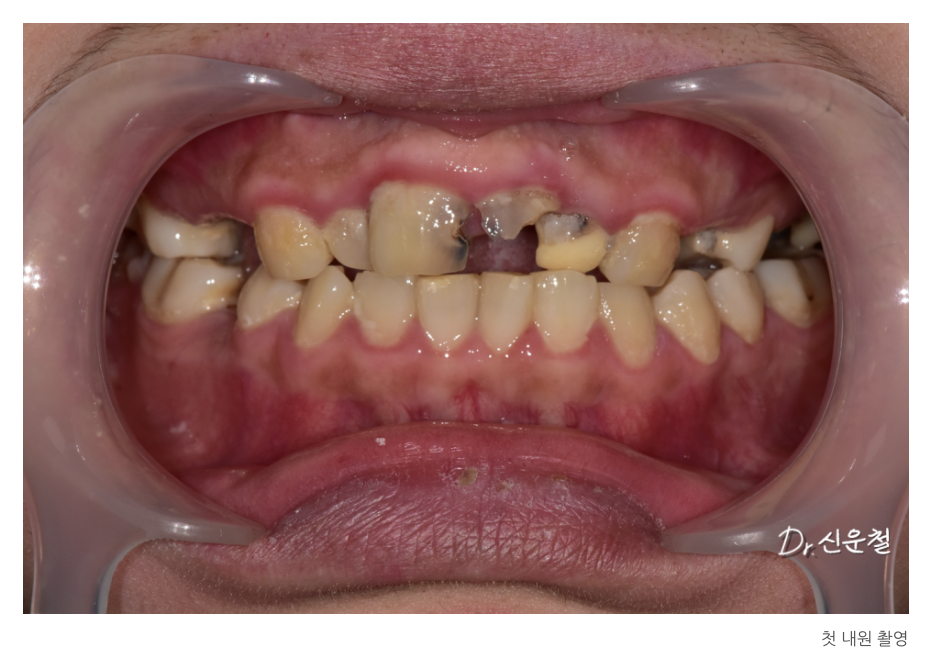

이번에 내원하신 환자분은

치과 공포증으로 오랫동안 진료를 미루어온 30대 초반 여성이었습니다.

진단 결과

여러 부위의 충치와 결손치,

그리고 임플란트가 필요한 부위가 확인되었습니다.